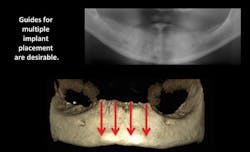

The percentage of general dentists who place implants is increasing significantly. Although implant placement has been common in dentistry for more than 30 years—performed primarily by freehand placement—guided placement is growing rapidly. Cone-beam radiography is necessary for fabricating implant-placement guides (figure 4). Research on guided placement shows that placing an implant with a guide constructed from a cone-beam image is somewhat more predictable and acceptable than freehand placement. This is especially true for the placement of multiple implants (figure 5).

Figure 4: Cone-beam images show minimal facial-lingual bone in the mandibular anterior area, requiring either small-diameter implants, bone grafting, or vertical removal of thin facial-lingual bone before placing implants.

Figure 5: Cone beam shows lack of bone in the posterior mandible and provides essential information about planning and placing four parallel implants in the mandibular anterior area.